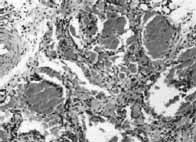

Se presentan macroscópicamente como tumores proliferativos (foto 1) e histológicamente, se caracterizan por presentar una hiperplasia endotelial con o sin lámina vascular y un incremento en el número de células de la matriz durante la fase proliferativa; fibrosis e infiltración grasa, disminución de la celularidad y un recuento normal de la células de la matriz durante la fase involutiva.(foto 2)(1,7)

Foto 2. Hemangioma fase involutiva